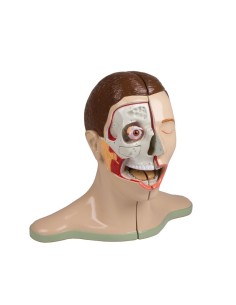

Dal cranio in 22 parti con incastri magnetici ai modelli di colonna vertebrale, da quelli di articolazioni a quelli di cuore, ogni pezzo della nostra collezione è progettato per un’immersione totale nello studio dell’anatomia umana. I nostri modelli, realizzati tramite scansioni di ossa vere, garantiscono un’esperienza tattile autentica e una fedeltà di peso quasi identica agli originali.

Essenziali per studenti e professionisti, i nostri modelli anatomici sono strumenti didattici che permettono di osservare le strutture anatomiche con precisione, eliminando la necessità di dissezioni o studi invasivi. Sono inoltre utili per spiegare ai pazienti le patologie, rendendo la comunicazione più efficace e risparmiando tempo prezioso.